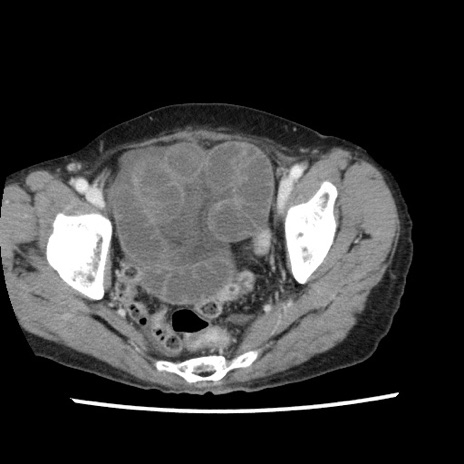

症例1(横断像)

【症例】80歳代女性

【主訴】腹痛

【現病歴】8時間前から腹痛あり来院。

【既往歴】糖尿病、脂質異常症、子宮体癌にて子宮全摘術

【身体所見】意識清明・会話良好だが腹痛で苦悶様、全腹部にわたって反跳痛と圧痛あり

【データ】WBC 13600、CRP 0.14、LDH 224、CK 90